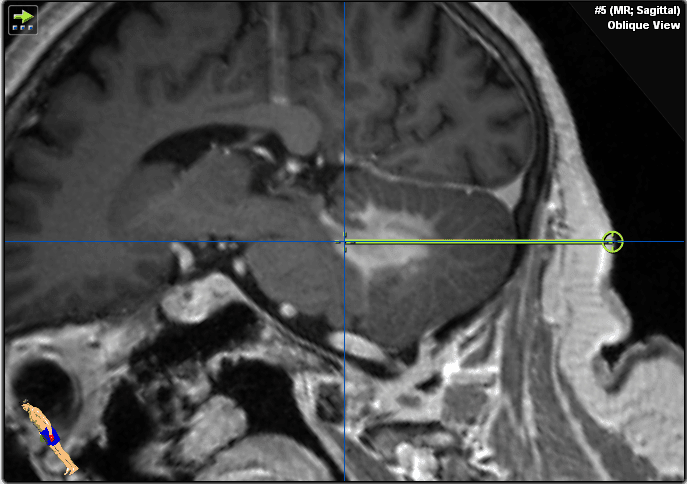

She underwent MR-imaging that showed a homogenous contrast-enhancing lesion adjacent to the fourth ventricle in the cerebellar tissue and moderate perifocal edema (Figures 1–2). Brainstem and cerebellar pedunculi were not involved. No signs of hemorrhage or ischemia were detected.

Figure 1. These gadolinium-enhanced T1 weighted images show an infratentorial lesion in the cerebellum and left cerebellar peduncle adjacent to the fourth ventricle. Please note the homogenous contrast enhancement suspicious of CNS lymphoma and missing infiltration of the brain stem.